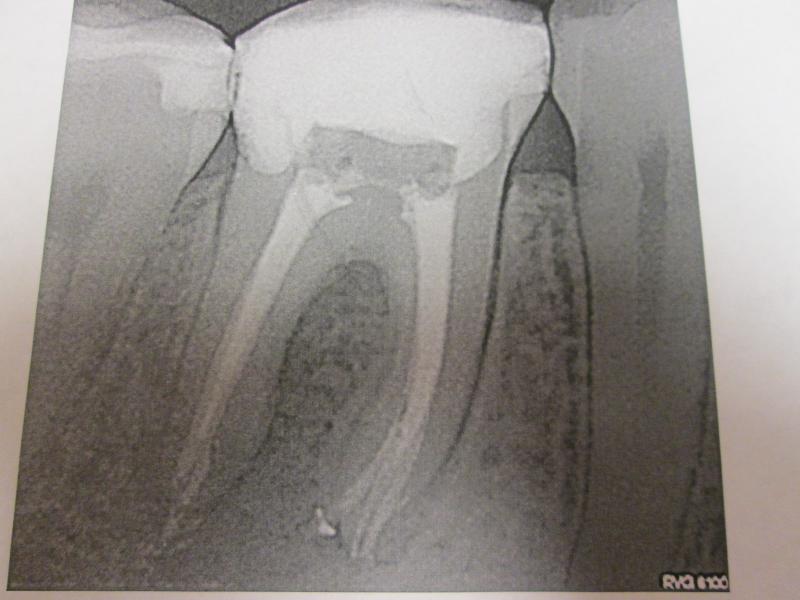

"DR. JET'S MISSION IS TO PERFORM  ROOT CANALS FOR A REDUCED FEE USING THE LATEST TECHNOLOGY  AND TECHNIQUES TO SERVICE THE MANY PEOPLE WHO ARE UNINSURED OR UNDER-INSURED GIVING EVERYONE AN OPPORTUNITY TO SAVE THEIR TOOTH!"

**PLEASE BE AWARE THAT  A ROOT CANAL IS AN ATTEMPT TO SAVE YOUR ALREADY DAMAGED TOOTH.  THERE IS NO GUARANTEE THAT ANY TOOTH CAN BE SAVED BUT DR JET WILL DO HIS BEST TO HELP YOU. THE OTHER OPTION IS TO EXTRACT YOUR TOOTH